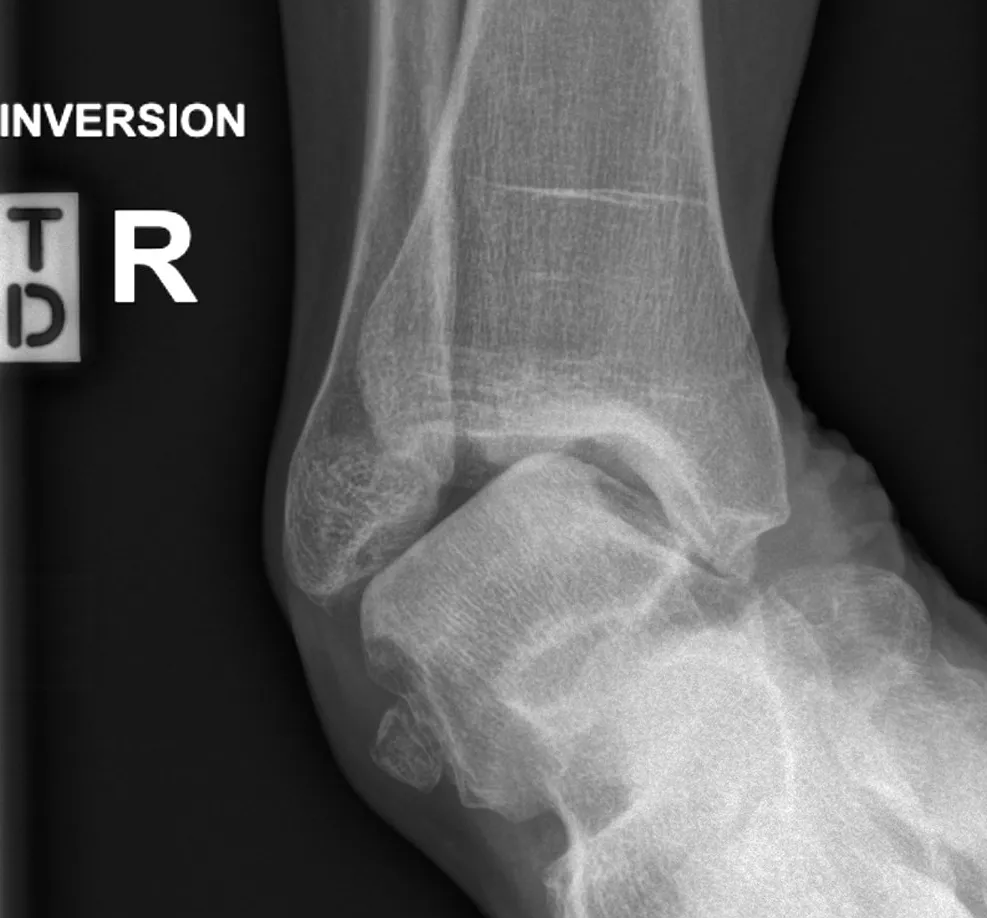

- examination of gait, leg and foot shape, ligament laxity (see images) and tendon function

- weight-bearing X-rays of the ankle.